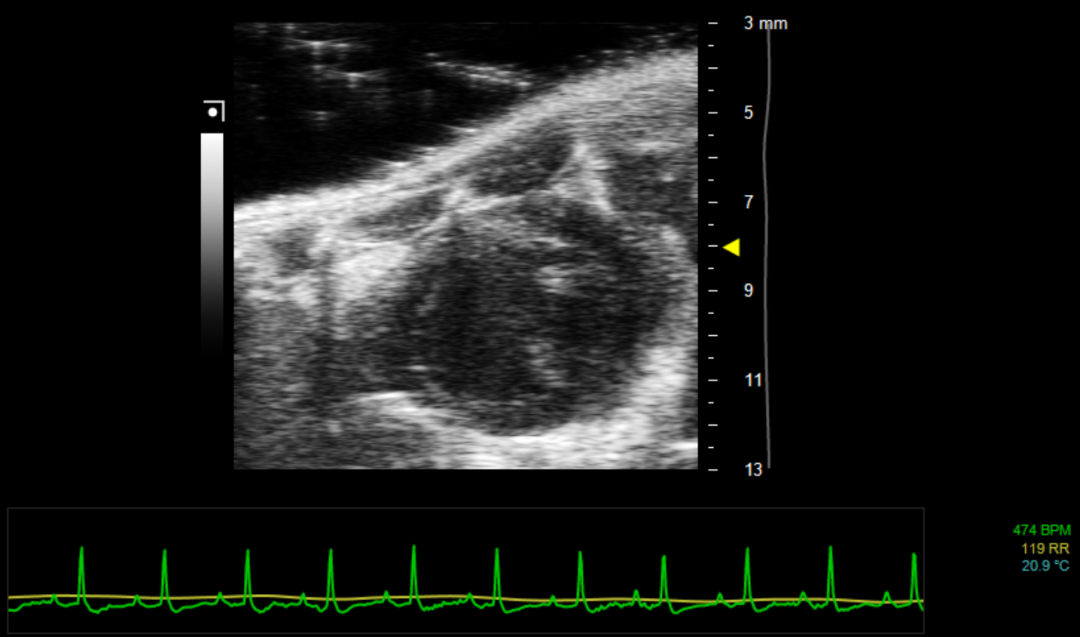

5. 在精准获取左心室胸骨旁长轴切面后,旋转探头90度,即可获取左心室胸骨旁短轴切面,探头约朝向下午两点钟方向,如图3所示,此时微调操作台Y轴,选择室腔最大面即为标准左心室胸骨旁短轴切面。该切面状态下可明显观察到乳头肌,且乳头肌分别位于下午两点及四点方向。获取画面如图4所示。

图4 左心室胸骨旁短轴(B-Mode)